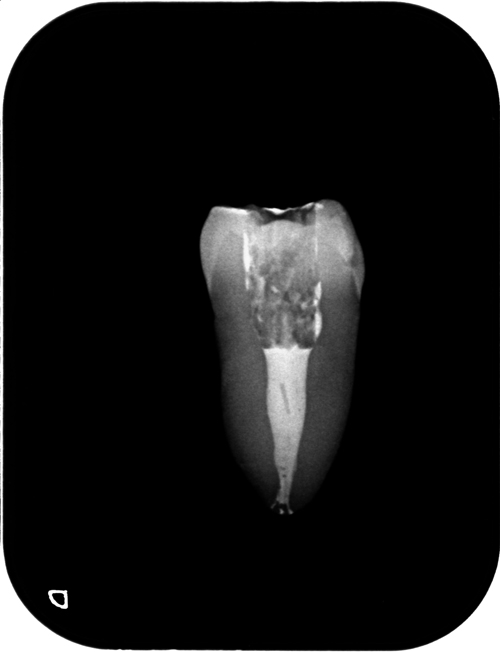

動画をご覧になるのが手っ取り早いのですが、入り口は二つでも中でクロスしている根管です。治療中にも何となくは解るのですが、吸引するとよく分かります。

抜去歯でのMTA根管充填のトレーニング。

どこをとっても物性は完璧なMTAですが、たった一点操作性の異常な悪さが問題です。根管に充填するのは簡単ではありません。そこでいろいろな方法があるのですが、これはニッケルチタンファイルをエンドモーターで逆回転してコンデンスしています。EMR連動での回転コントロールはやっぱり便利です。

ところでMTAはこういった練習に使用するには大いなる勇気が必要です。要するに高いのです(汗)。ところが偶然練習用の粉を見つけました。もうMTAは10年以上の使用歴がある私ですが、練習で使用してみて違いが全く分かりません。使いづらいのも練った感じも、練ったあとすぐに乾いてきてボソボソになるのもそっくりです。この動画で使用しているのもその粉です。硬化しないので洗い流して練習用の歯を再利用できます。そしてこれがまた絶妙なのですがX線造影性があります。世紀の大発見です! トレーニングにしか使えないのが欠点です(当たり前)。セコイけどここで書いてしまうのは惜しいので内緒(笑)。友人限定で教えます。ポルトランドセメントで練習するよりずっとず〜〜〜っと良いよ。